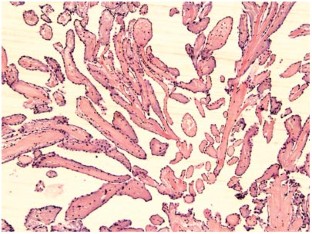

Investigations Physical examination, chest radiography, laboratory testing, electrocardiography, transthoracic and transesophageal echocardiography, multislice-CT coronary angiography, pathological and histological examination of the surgically excised tissue.

Diagnosis Papillary fibroelastoma of the aortic valve in conjunction with coronary artery disease.